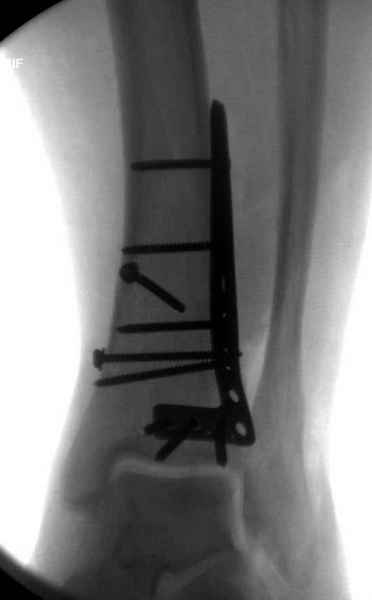

После ExFix проведение компьютерной томографии считаем обязательным, получаем информацию о расположении крупных фрагментов, которая подскажет сторону операционного доступа и направления проведения фиксирующего материала.

Любая фиксация - преконтурированные пластины с уголовой стабильностью, медиальная, латеральная в зависимости от нахождения отломков или наружная фиксация типа аппарата Илизарова подходят для ранней мобилизации.

Не все переломы пилона фиксируются медиальной

пластиной, поэтому, учитывая что большой фрагмент

находится на латеральной стороне, я бы применил

передне-латеральную пластину.